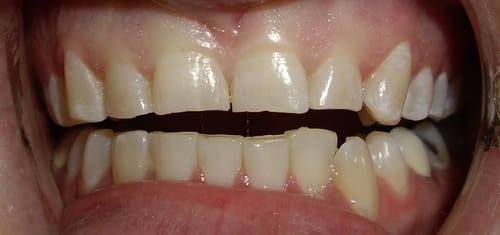

Before And After Dental Treatment

Before / After

From stained or misaligned teeth to a radiant, confident smile, our results speak for themselves. See the difference professional dental treatment can make — and imagine what we can do for you.